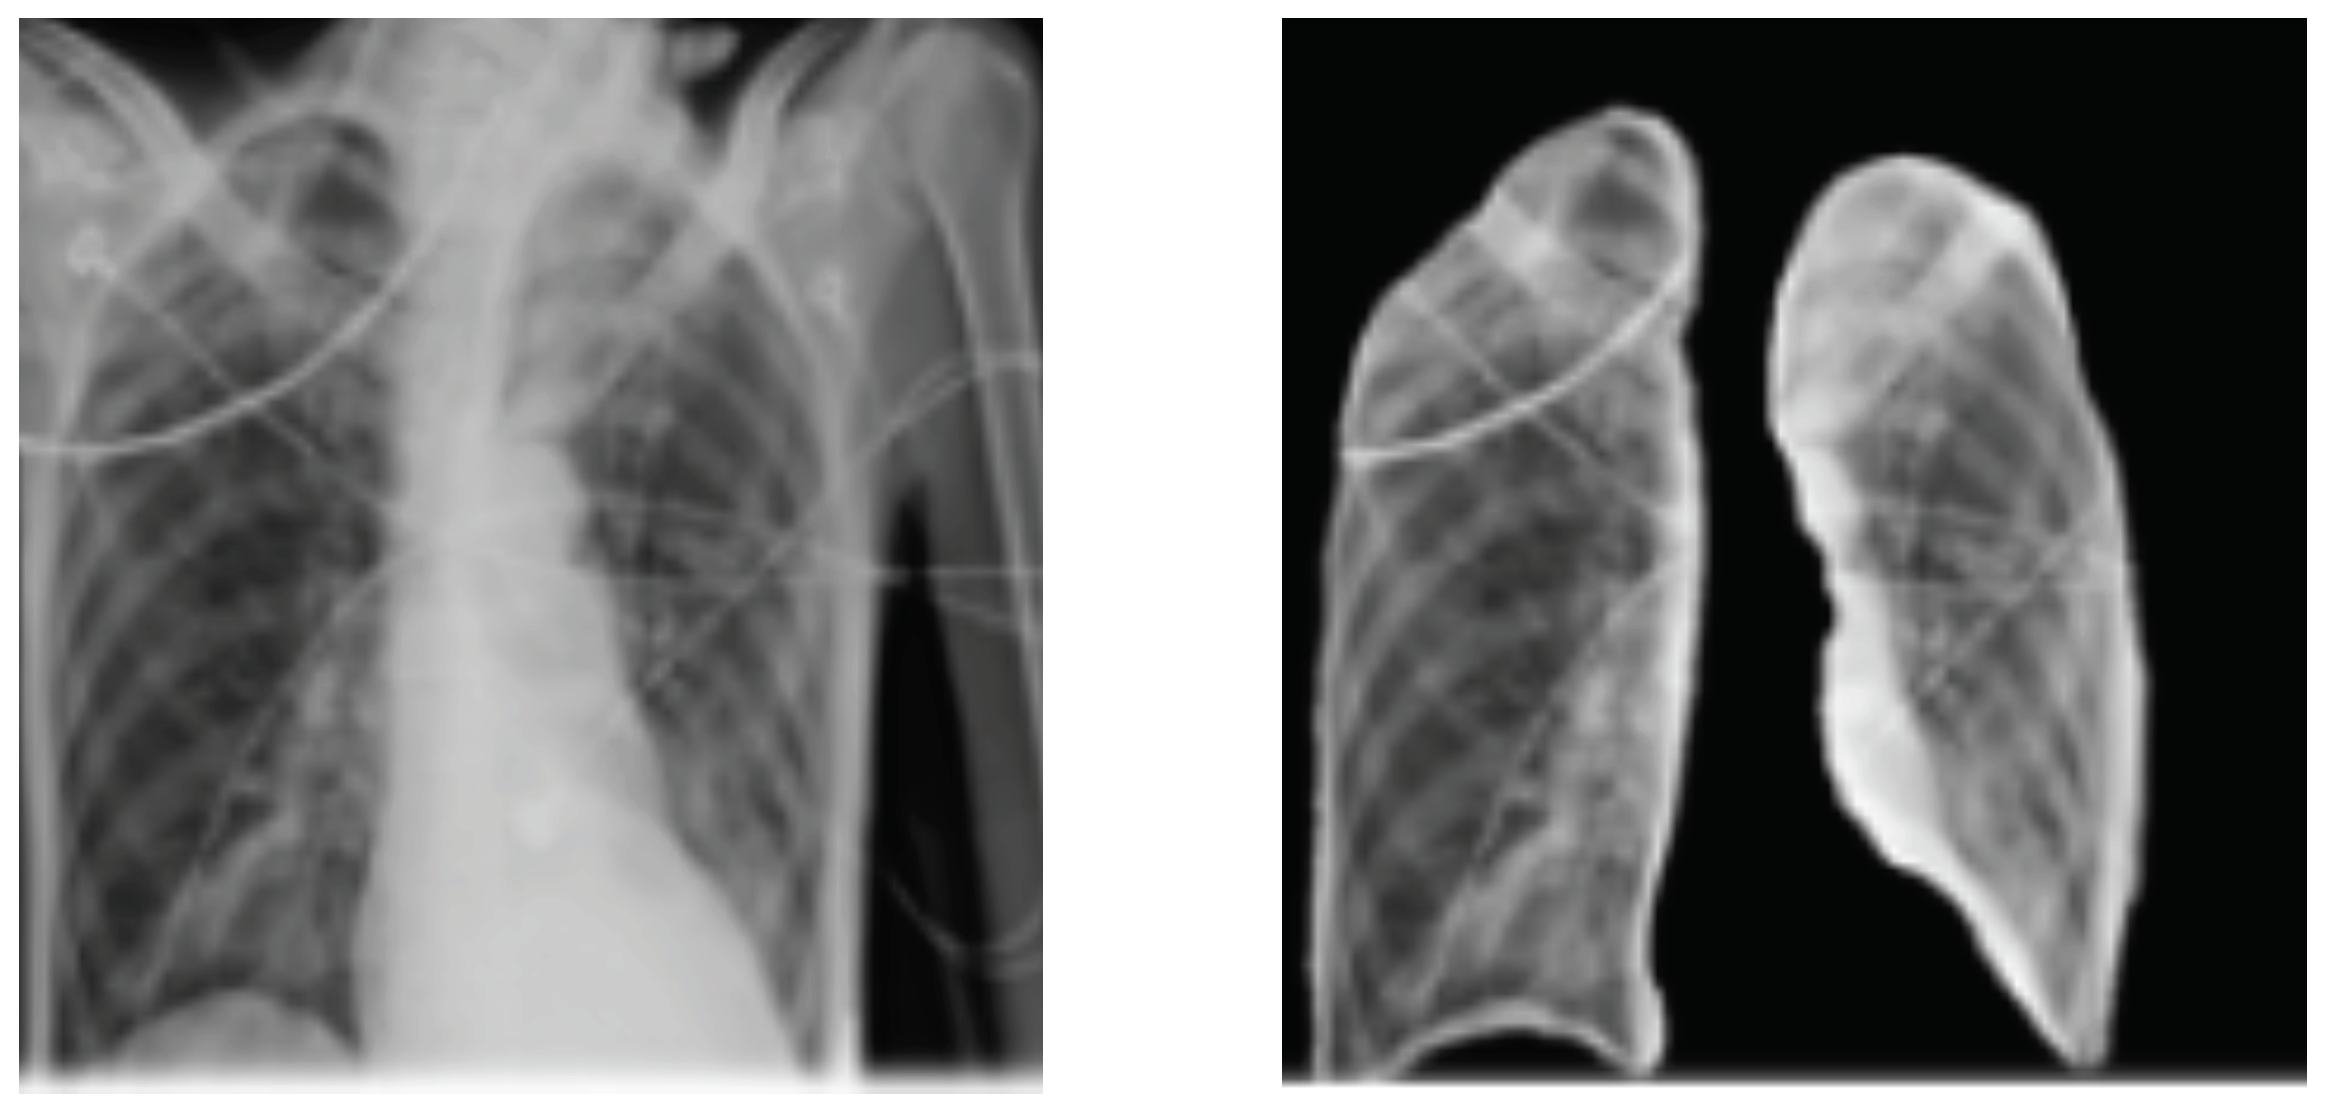

4.1. Data Sets

4.3. Results Analysis